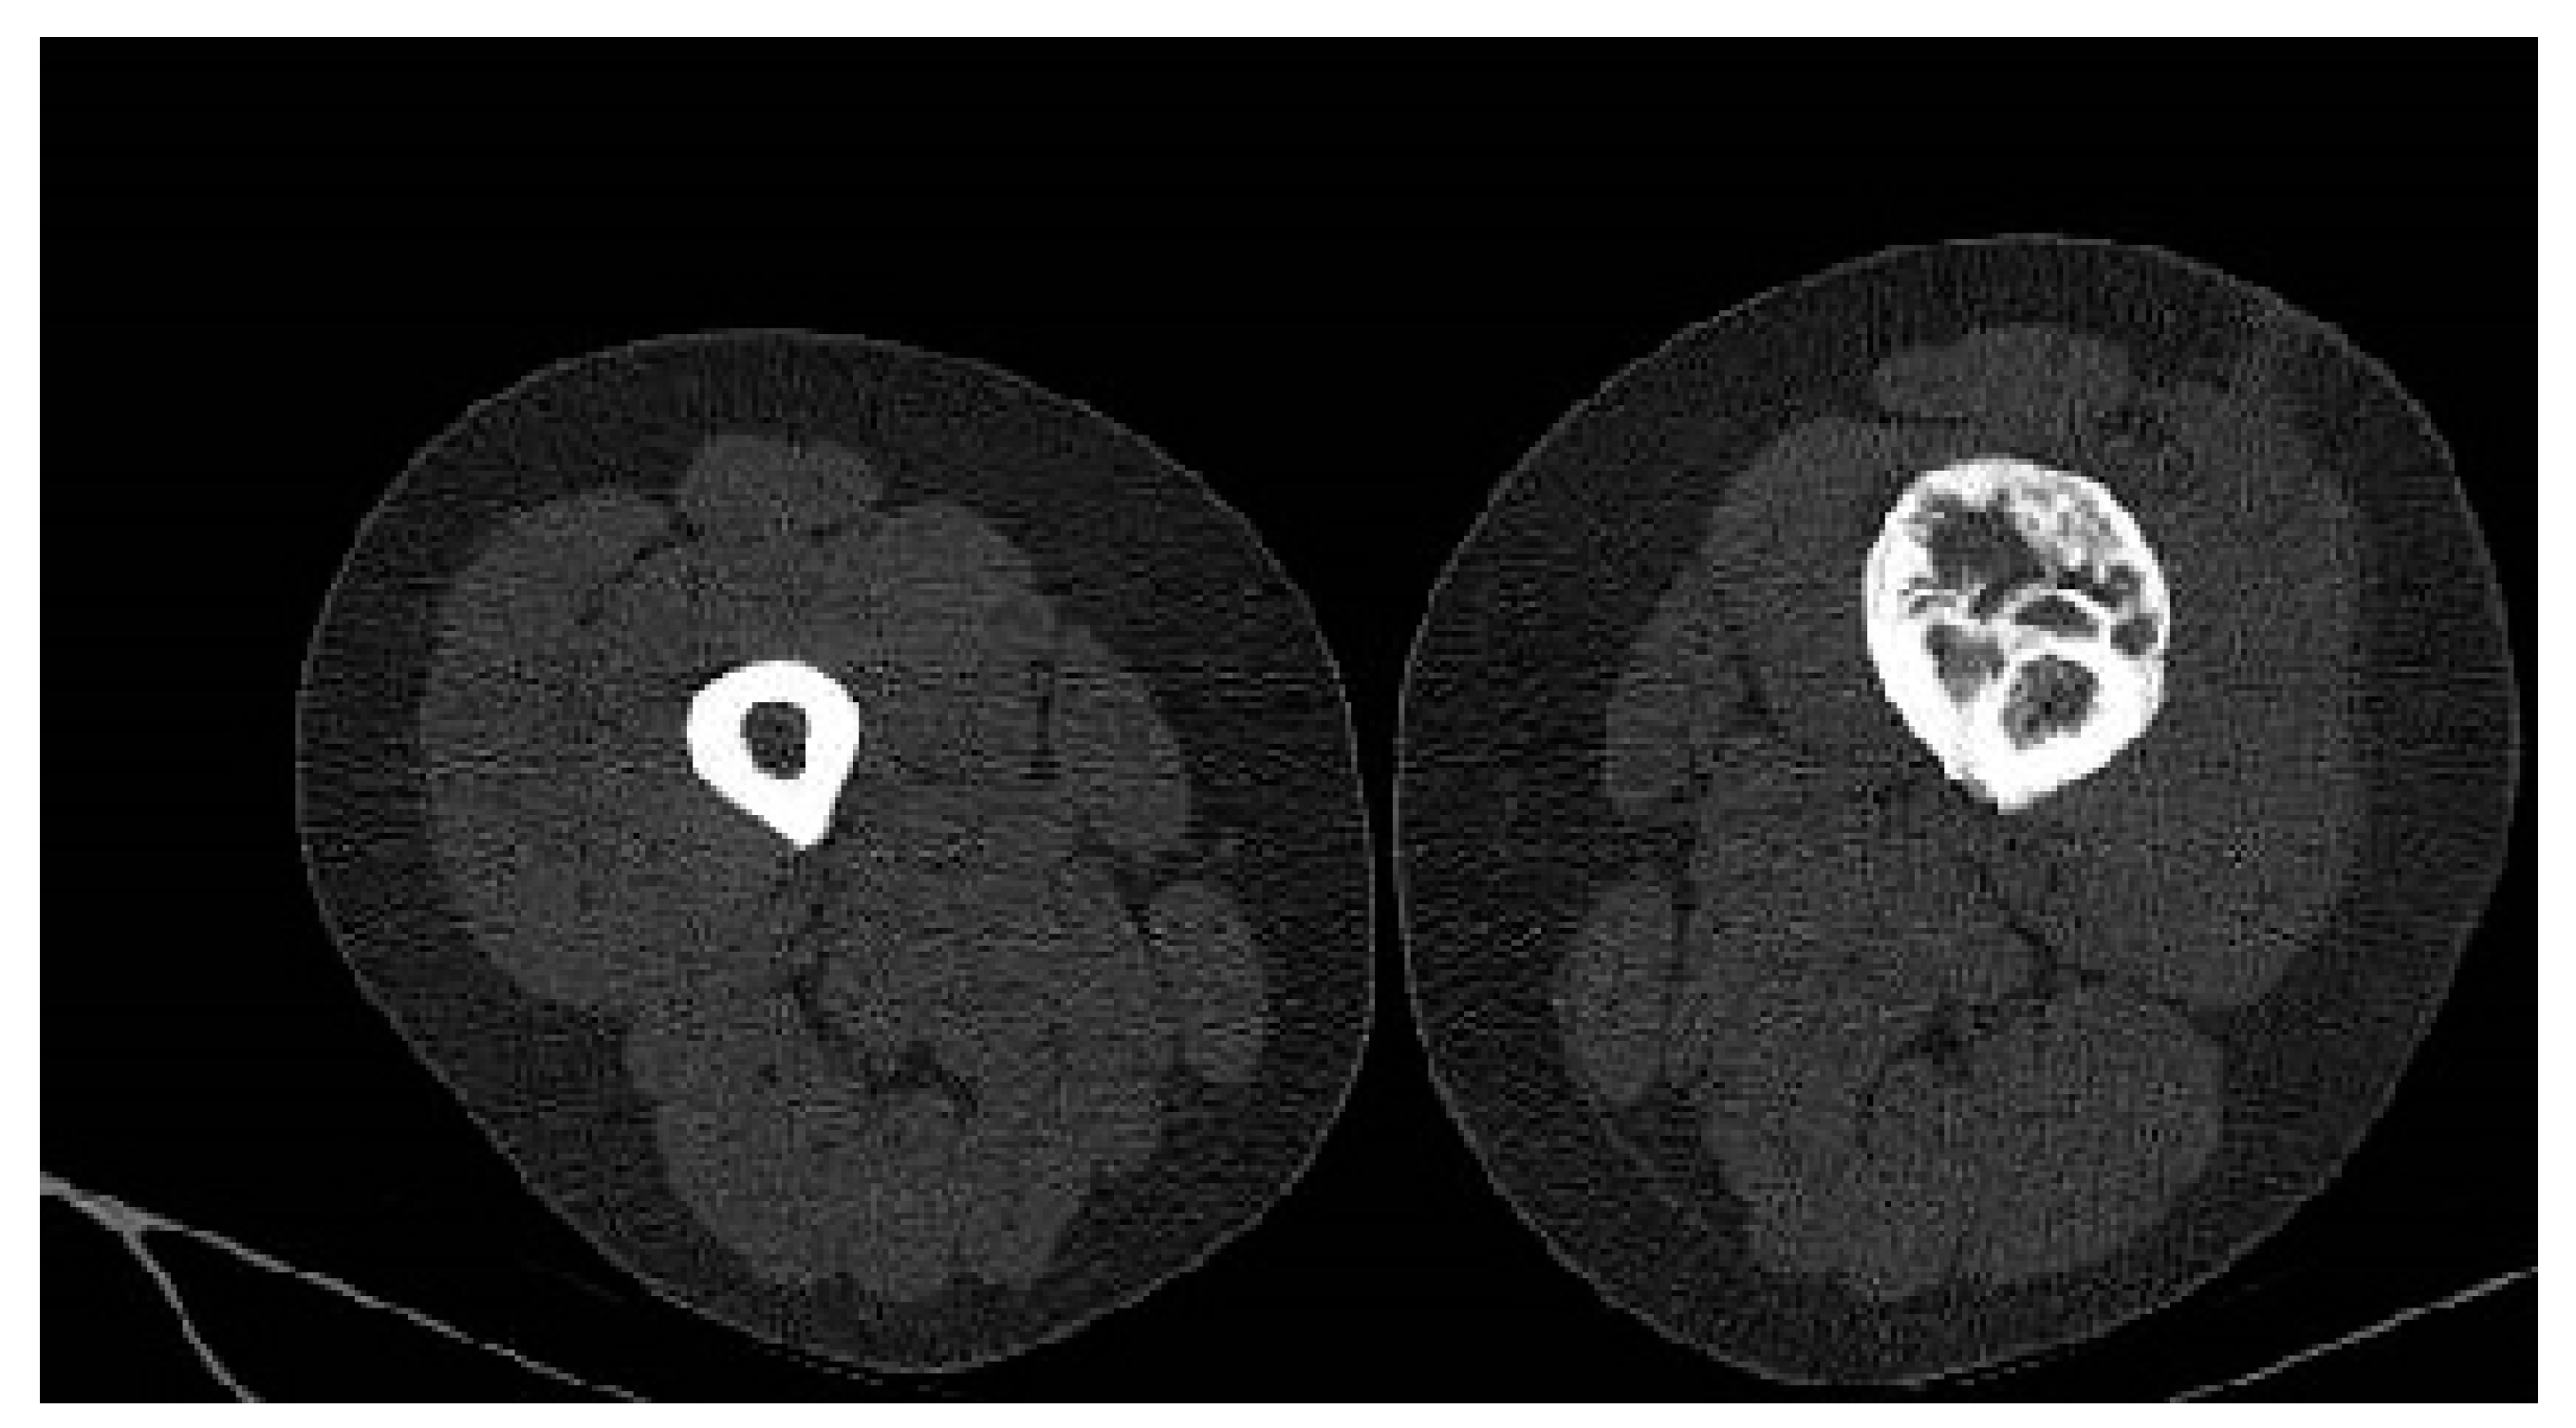

Considering the size of the lesion, the imaging aspect, and the clinical symptomatology, a differential diagnosis with parosteal osteosarcoma was required. A CT scan of the thorax, abdomen, pelvis, and left thigh was performed. The CT examination showed no oncological changes in the thoracic, abdominal, and pelvic regions; however, on the femoral shaft, there was a localized cortical and pericortical bone lesion formation that surrounded approximately 180 degrees of the femoral shaft (anterior, medial, and lateral). It had a predominantly sclerotic structure but was associated with lytic areas with thickening of the bone cortex and areas of periosteal reaction (Figure 3).

Figure 3. Axial CT scan showing a sclerotic bone with lytic areas of thickening of the bone cortex and areas of periosteal reaction.